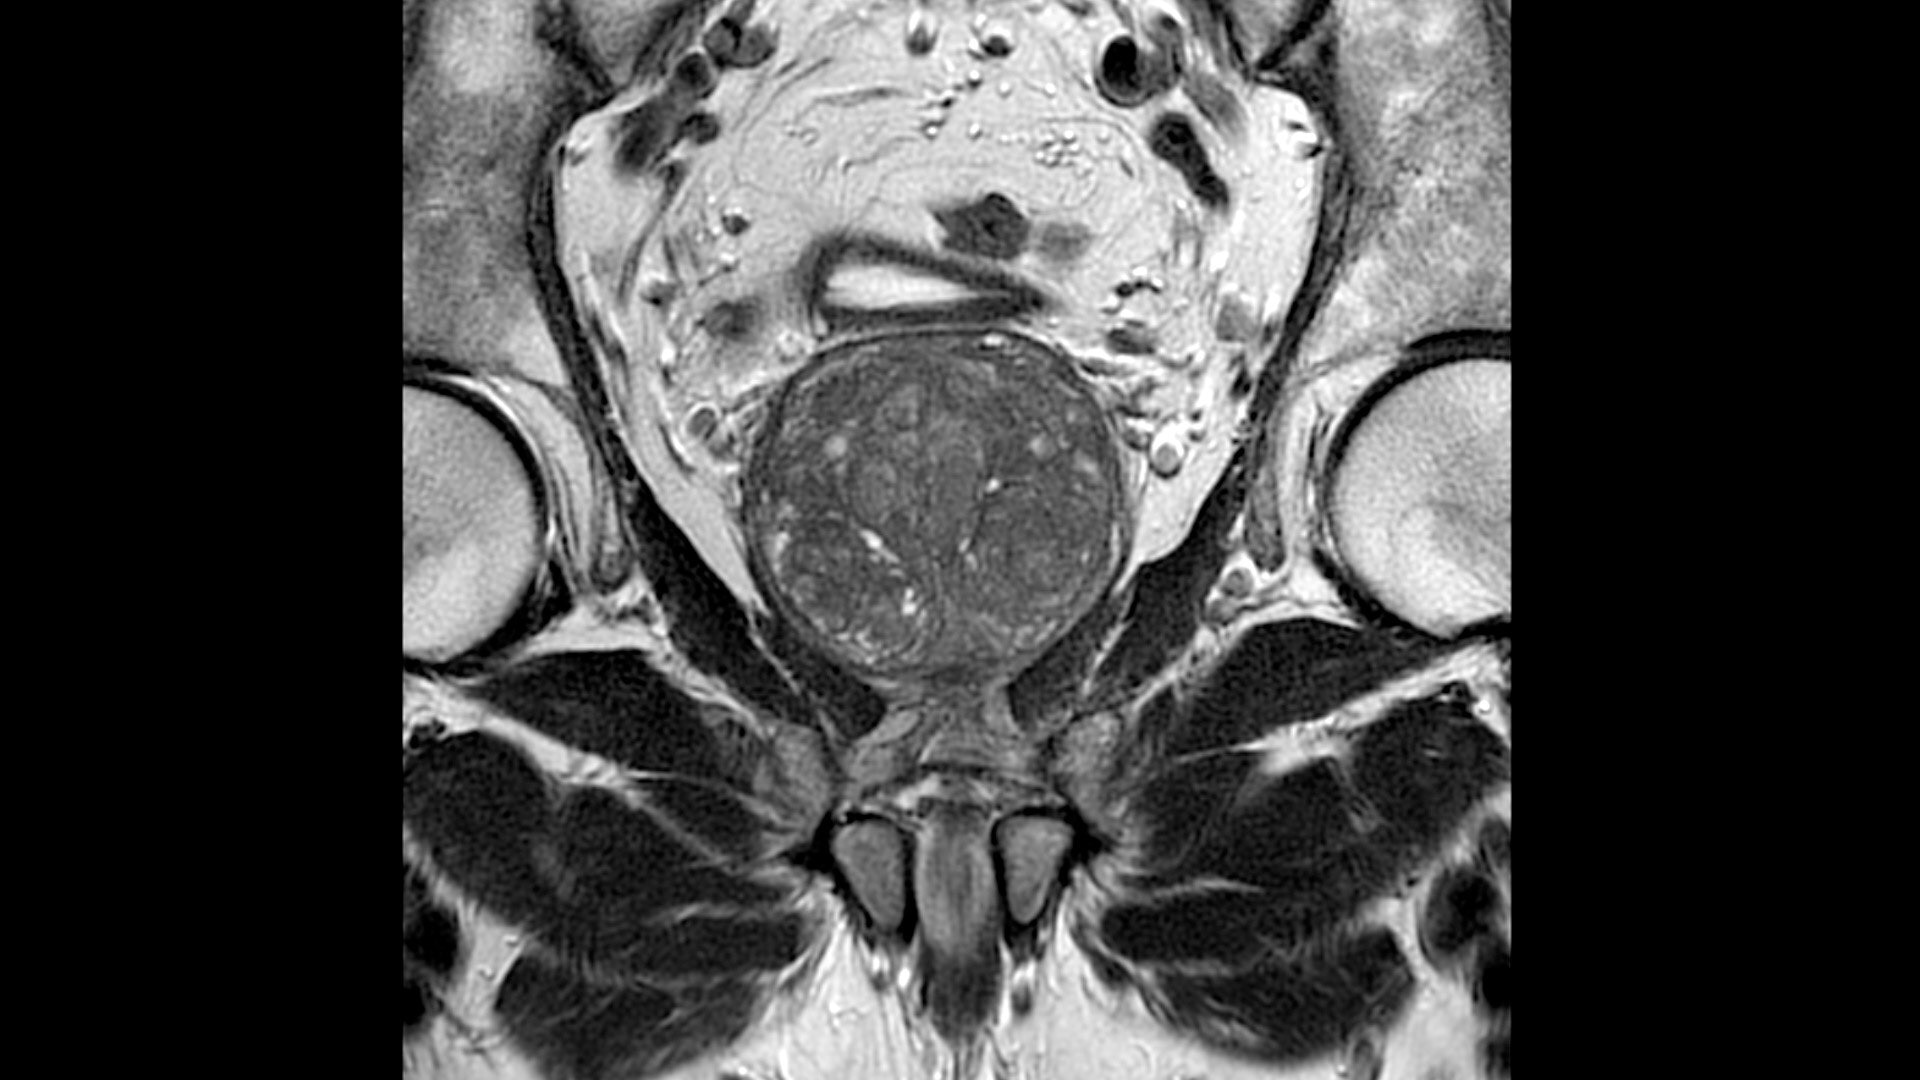

• Flexible, ultra-low profile design to fit all sizes, shapes and ages

• Positioning freedom with previously hard-to-scan anatomies

• 20-ch and 21-ch design to accommodate all patient sizes and anatomies